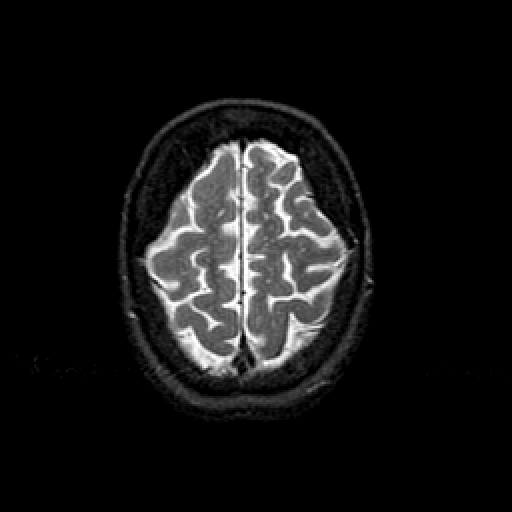

T2-weighted structural MR: Slice 44

Slice 44